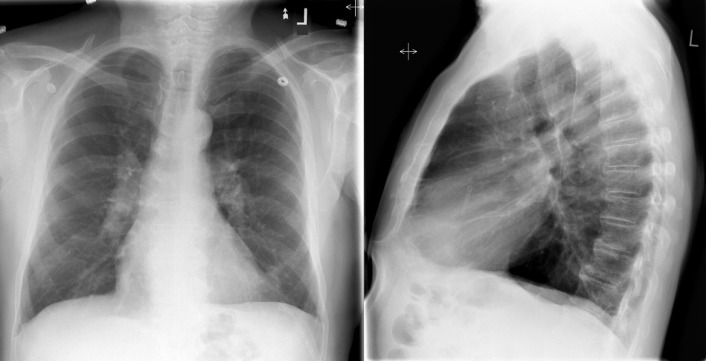

A patent foramen ovale is present in 25% to 30% of the adult population ( Figs. 18-1 to 18-4 ). Any magnitude of shunting across it in normal circumstances is undetectable radiographically. Percutaneous patent foramen ovale closure devices are fairly commonly inserted and are radiographically evident.